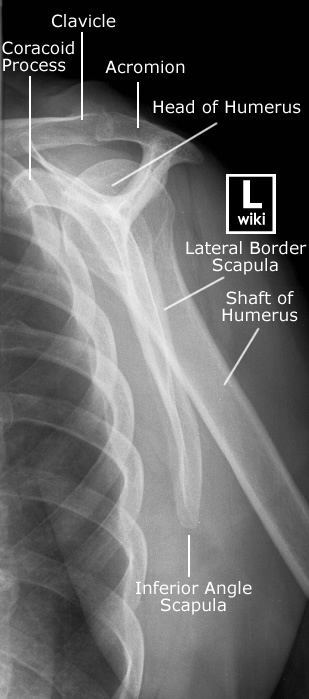

| Lateral View | Neer View |

![]() |